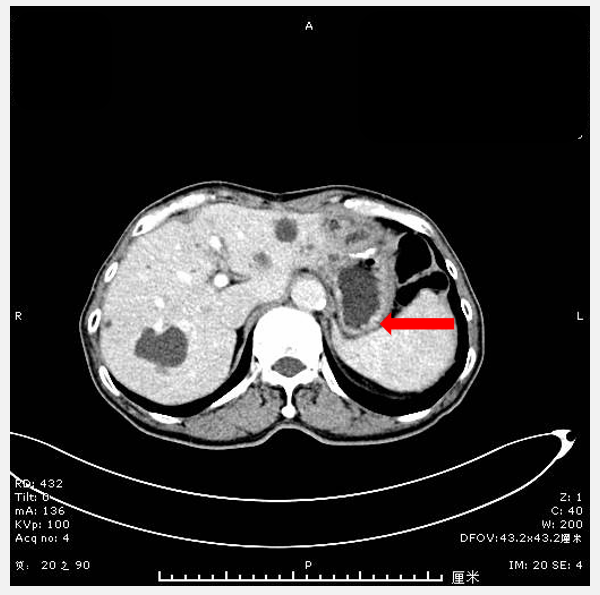

2024年11月7日门诊复查胸部及全腹部强化CT示左侧肾上腺外侧肿块考虑转移。移(图1)。2024年11月12日PET-CT结果示肠系膜上静脉右旁及左侧脾静脉后方转移瘤。